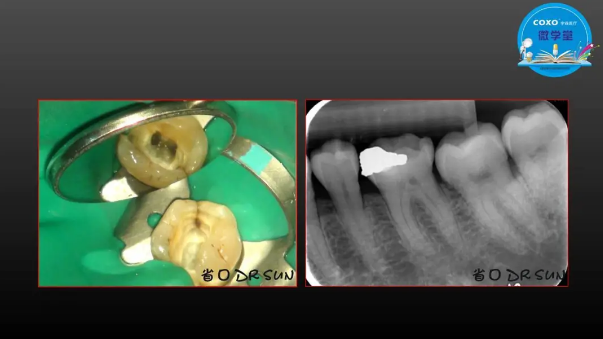

主任醫(yī)師,牙體牙髓副主任, 廣東省口腔醫(yī)院牙體牙髓科 主任醫(yī)師。2003年碩士研究生畢業(yè),研究方向?yàn)檠荔w牙髓病學(xué),擅長(zhǎng)于牙體牙髓病的診斷、齲齒、牙髓炎、根尖周病的治療以及前牙美容修復(fù)。